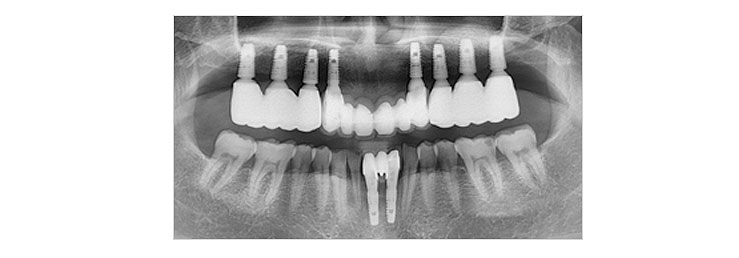

보철물 장착

임플란트의 기둥(지대주)위에 인공치아를 만들어 넣는 과정입니다.

임플란트 시술 후 관리를 잘하지 못한다면 교합이상 또는 임플란트 주위염 등이 발생될 수 있습니다.

종로사과나무치과의 Dental care system으로 지속적인 사후관리를 통하여 안전하고 건강한 치아관리를 받으실 수 있습니다.

임플란트 시술 후 구강 위생 관리를 철저히 잘하면 반영구적으로 사용할 수 있습니다.

그러나 구강 위생 관리를 소홀히 하면 자연치아에서 생기는 치석, 잇몸병, 풍치 등이 임플란트에도 똑같이 일어나 수명을 단축시킵니다.

오래 사용하기 위해서는 임플란트 수술 후 철저한 구강 위생 관리와 담당 의사선생님의 지시에 따라 정기적인 구강검진이 필요합니다.